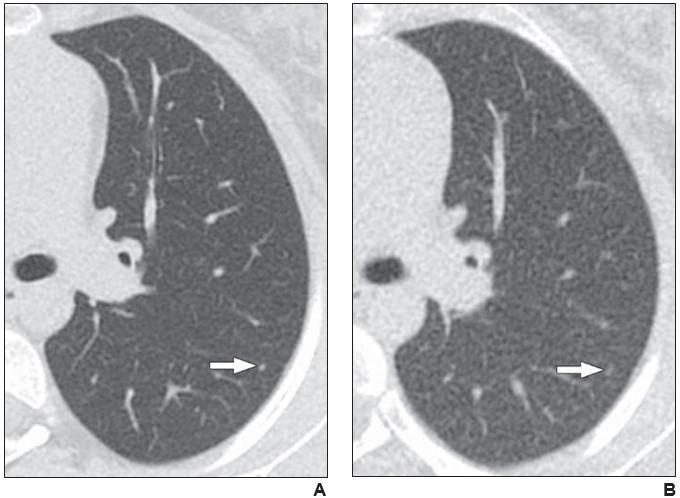

image: Axial reformatted clinical (1.083 mSv) and reduced dose (0.318 mSv) CT images from a 17-year-old girl with osteosarcoma. A 2 mm left lower lobe nodule is clearly visible in the left lower lobe on the clinical CT image (arrow in A). The same nodule is vaguely apparent on the reduced-dose CT image (arrow in B), classified as present but poorly visible.

Among the 78 patients (44 male, 34 female; mean age, 15.2 years) with cancer who underwent standard-dose chest CT and reduced-dose chest CT (mean effective dose 0.3 ± 0.1 mSv, representing 83% dose reduction) in the same imaging encounter, the reduced-dose protocol detected greater than 90% of lung nodules identified on the standard-dose examination.